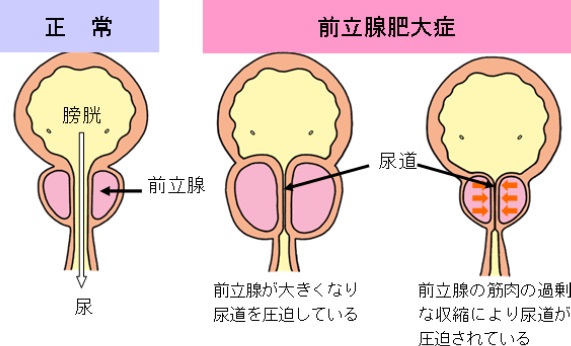

会陰部 男性-男性 感染後3~12日で会陰部や直腸粘膜に5~8mmのびらん・丘疹が発生します。 やがて潰瘍になりますが、痛みがなく数日で治ってしまうので、本人が気づかないことも多いです。 その後1~2週間で、鼠径リンパ節や大腿部リンパ節が腫れます。前立腺の病気には慢性前立腺炎、急性前立腺炎、前立腺肥大症、前立腺癌などがあります。 慢性前立腺炎 あまり知られていない病名ですが、罹患されている男性は多く、すでに治療 中でなかなか良くならず悩んでおられる方も多いと思われます。 命に関 わる病態ではありませんが、ご本人に

前立腺の病気 さくまクリニック

前立腺の病気 さくまクリニック

前立腺を学ぼう 男のストレスと慢性前立腺炎 扶桑薬品工業株式会社